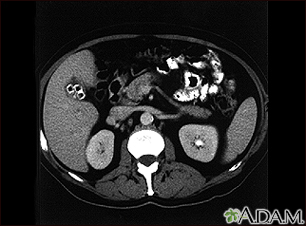

CholecystolithiasisBackCholecystolithiasisCholecystolithiasis. CT scan of the upper abdomen showing multiple gallstones. E-mail FormEmail ResultsName:Email address:Recipients Name:Recipients address:Message: